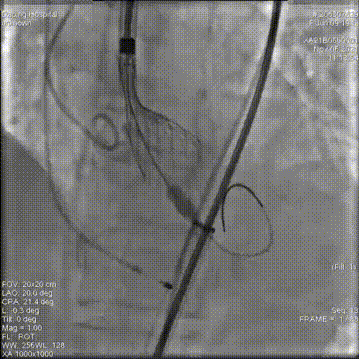

第一次释放,位置过高回收定位

第二次释放,位置过低再回收释放

第三次瓣膜释放定位